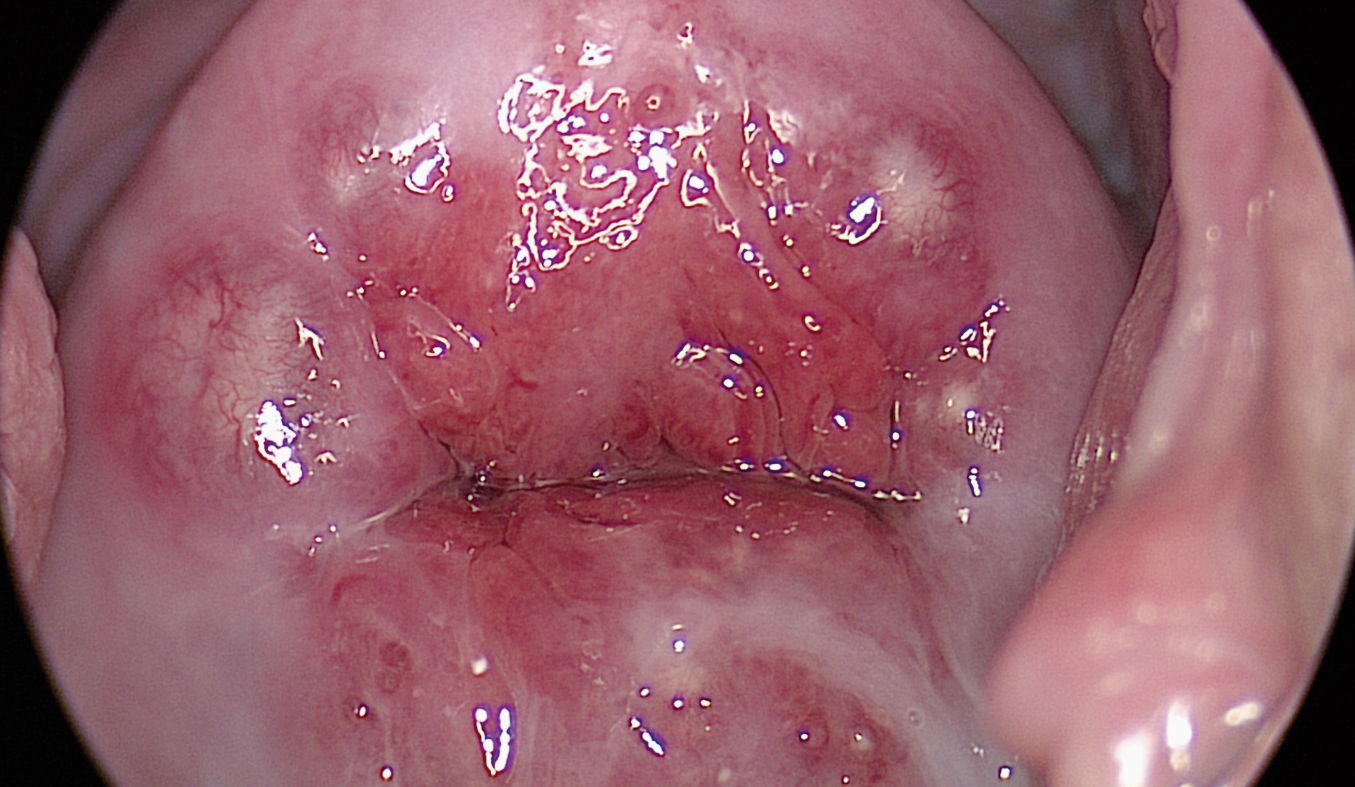

Typical transformation zone type 1 with Ovula Nabothi.